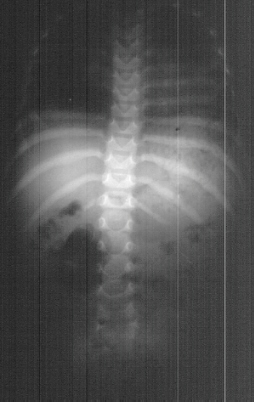

By age three there was concern about her spine. Radiographic evaluation

at age of 3 years was done(above).